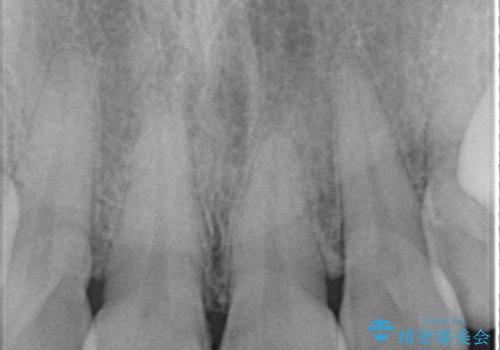

また、右上の前歯は裏側までヒビが入っていることや、1層構造のラミネートよりも2層構造のオールセラミッククラウンの方が色の再現性も高いことから、右上前歯1本のクラウン治療をおすすめしました。

今回は、歯肉炎があるため、その治療を行ってからクラウンを製作しました。